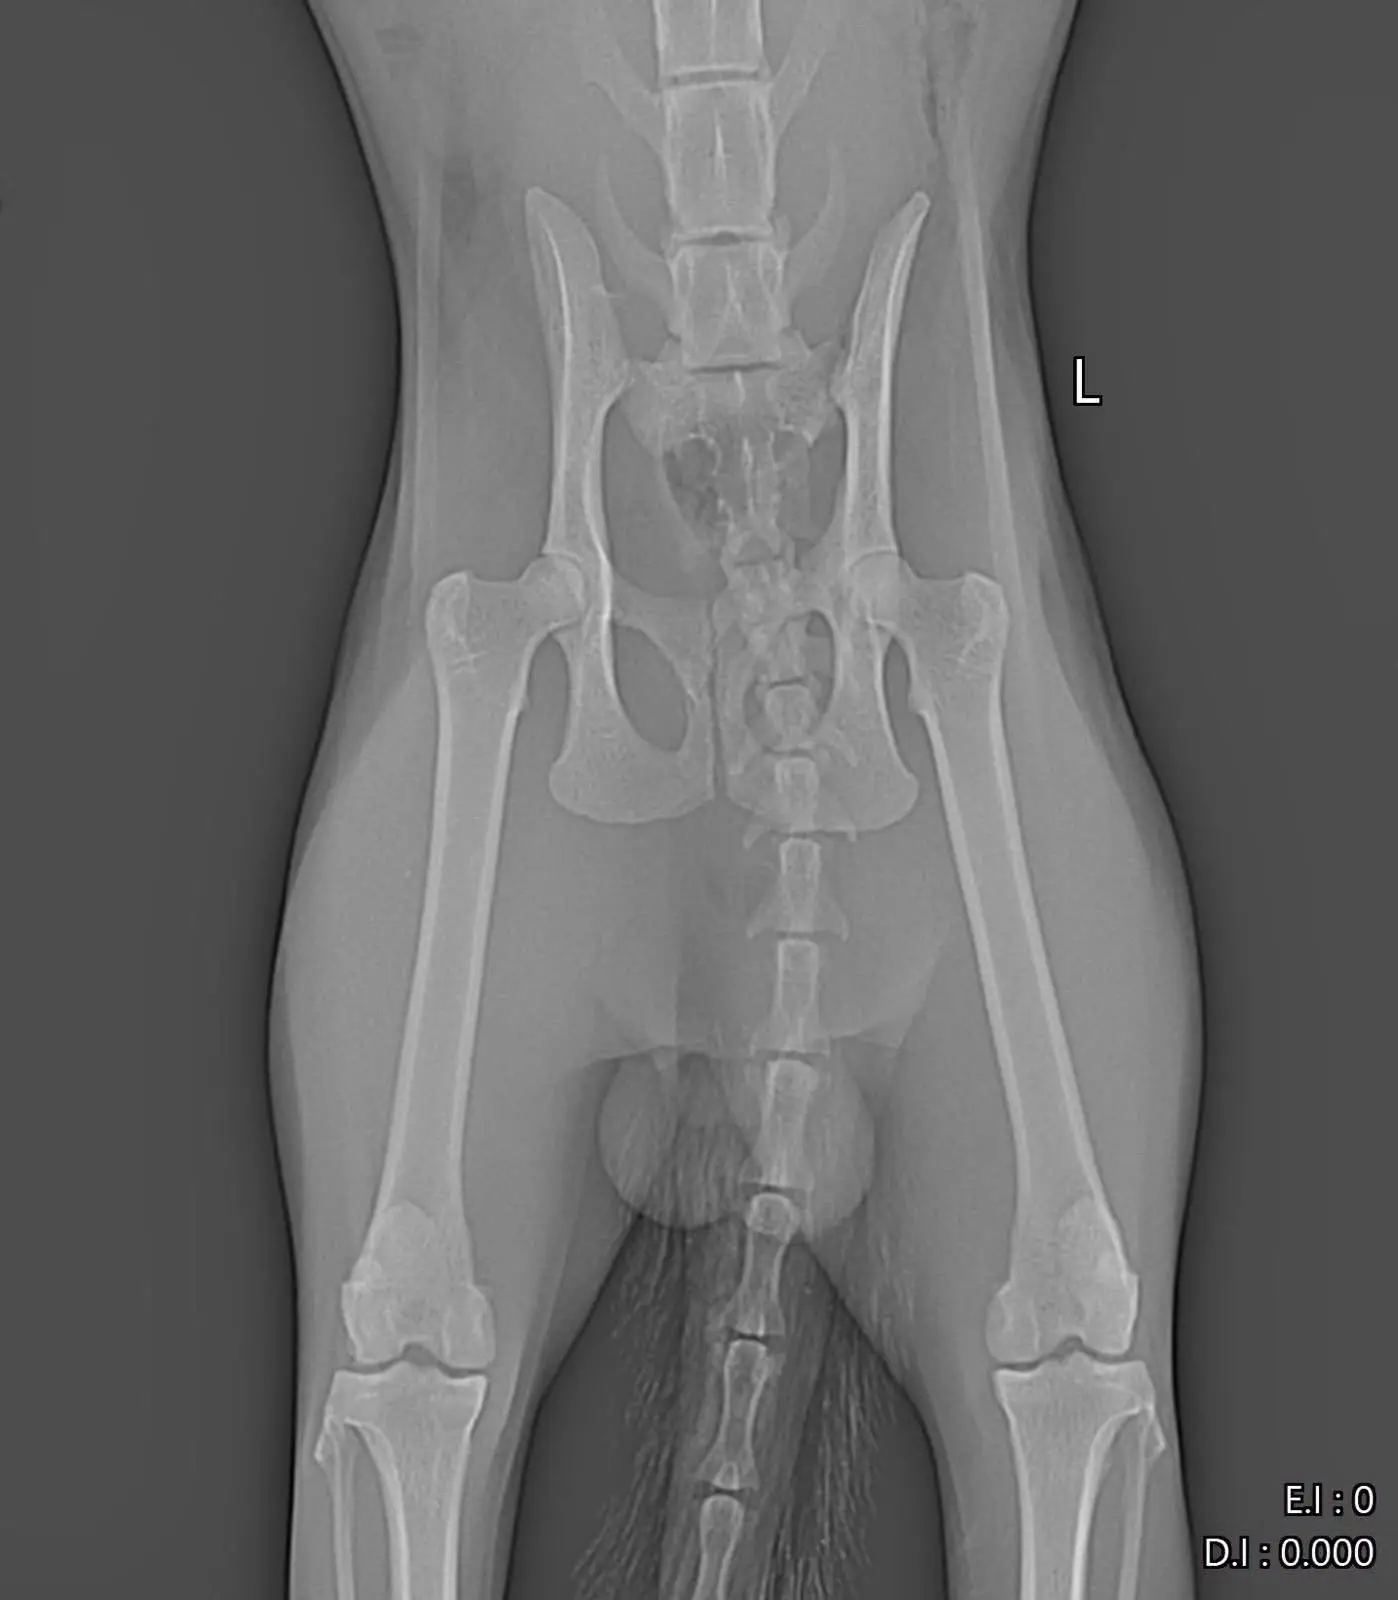

Илиян е пострадал тежко и болката му е огромна. Изследванията показаха:

Счупване на таза

Дислокация (изкълчване), която изисква спешна намеса. За да може това мило създание отново да ходи нормално, е необходима ортопедична операция.